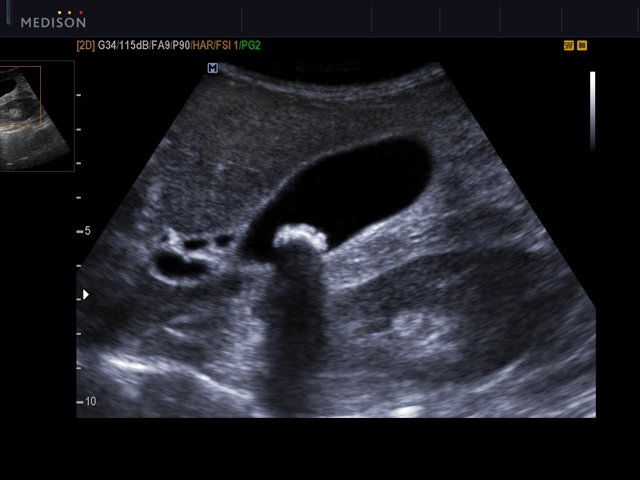

Прочитайте условие задачи. Рассмотрите эхограмму желчного пузыря. Опишите эхограмму и дайте ультразвуковое заключение.

Женщина, 43 года. Обратилась к гастроэнтерологу с жалобами на чувство переполнения эпигастральной области, иногда - тошноту в ответ на прием жирной пищи. При проведение УЗИ органов брюшной полости были замечены следующие очаговые изменения в желчном пузыре: